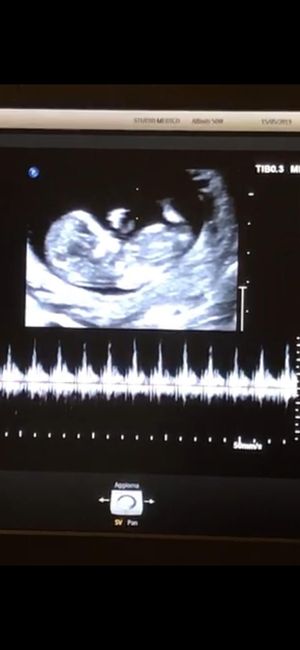

Esperte di Nub Theory a me

Da Claudia , Il 1 Novembre 2019 alle 11:07

Mancano ancora tantissime settimane alla morfologica, che avrò il 15 Luglio, mi ritrovo spesso a fantasticare se sarà Filippo o Lucrezia, io mi sento maschio ma non si sa...